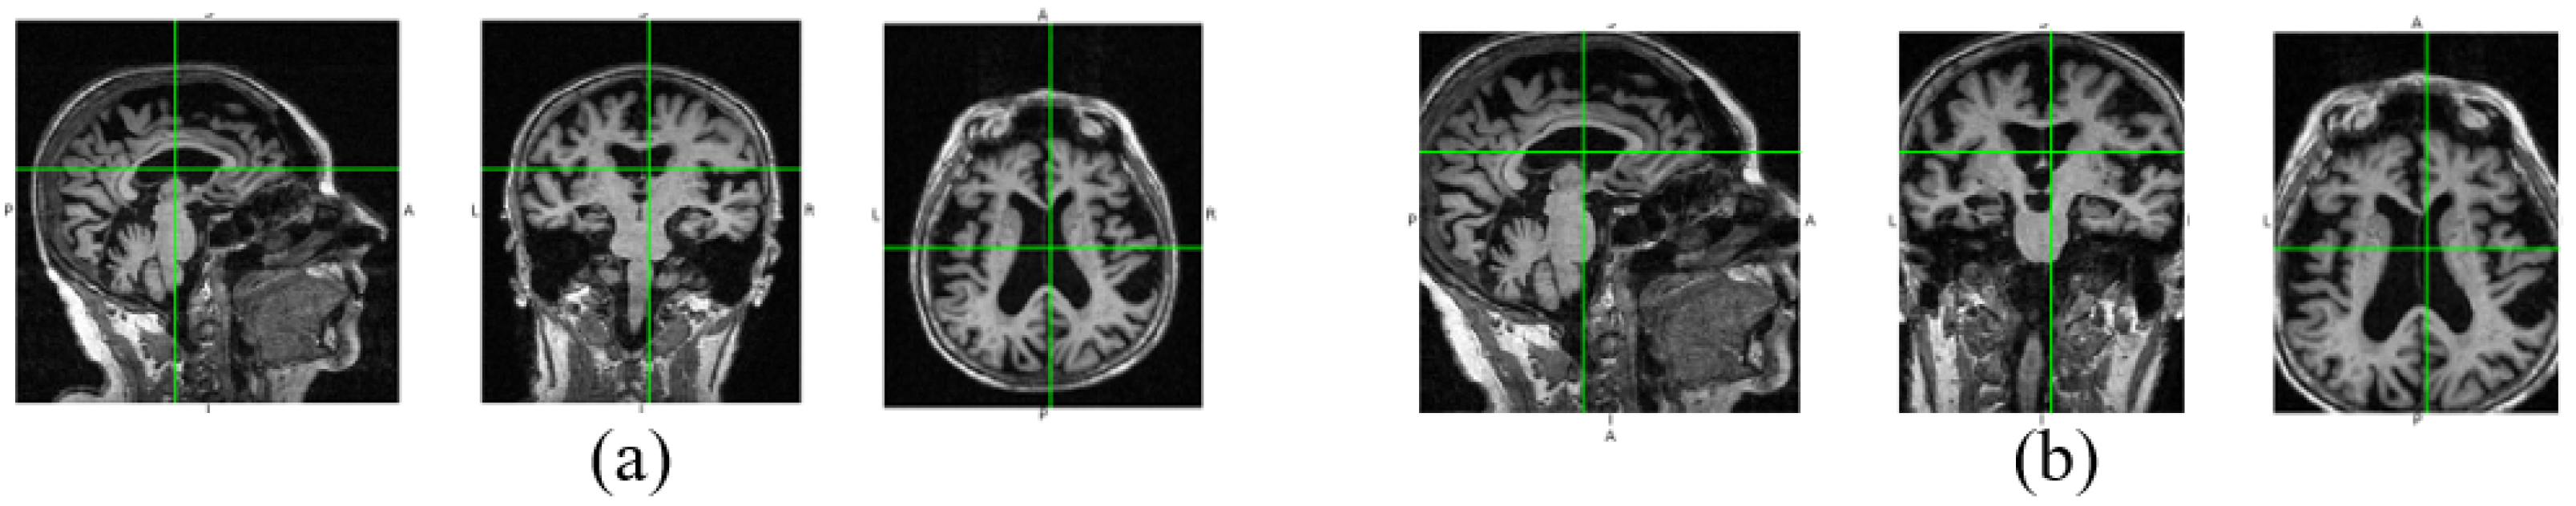

In Figure 3, we show the data changes before and after data denoising. Through data denoising, the noise regions in the raw 3D image are cut out, and the size of the data input into the neural network can be reduced from 192 × 192 × 160 to 160 × 160 × 120. Because the noise data is reduced, the neural network model can better extract useful features for diagnosis. In addition, data denoising helps to reduce calculation by decreasing parameters of the fully connected layer in our diagnosis network.

Figure 3.

Raw image and the denoised image. The three views of the raw image are shown in (a), and (b) is the corresponding denoised views.

We use the AD-image group and the NC-image group to explain our data denoising process. First, we obtain their mean images and according to Equation (1). Then the difference image is calculated according to Equation (2). By normalization, we can get the difference image with the voxel values between 0 and 1. Next we transform into its corresponding mask according to a given threshold . Finally, each AD-sample image and each NC-sample image are cropped according to the mask to achieve noise reduction. In this way, the lesion areas corresponding to large differences in an image will be preserved, and the useless voxels can be cut off. In Figure 3, we show the views of a raw image at three dimensions and their corresponding denoised views. It can be found that the useless information near the boundaries is reduced, but the main information is not lost. The implementation details of data denoising are shown in Algorithm 1.